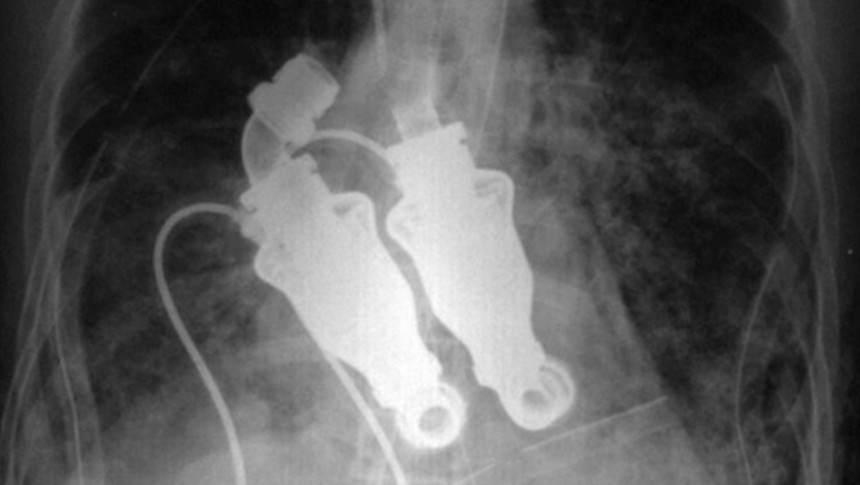

Крейгтің жұбайы Линда Льюистің келісімімен дәрігерлер оған жасанды жүрек алмастырғыш орнатты. Бұл құрылғы үй жағдайында жасалған бөлшектерден құрастырылған. Дегенмен, дәл осы құрылғы Крейгке тағы бес апта өмір сүруге мүмкіндік берді, ал бастапқыда оған небәрі 12 сағат өмір қалды деп болжанған еді.

Бұл жаңалық дәрігерлердің ұзақ жылдар бойғы зерттеулерінің нәтижесі еді. Операция алдында ғалымдар құрылғыны 50-ден астам бұзауға орнатып, олардың жүректерін алып тастап, зерттеу жүргізген. Бір күннен кейін жануарлар қалыпты өмірлерін жалғастырып, жүрек бұлшықетінің пульсациясынсыз қозғалып, тамақтанып, ұйықтап жүрген. Олардың қан айналымын жүрек емес, үздіксіз ағынды қамтамасыз ететін құрылғы реттеп отырған.

Бұл құрылғы арнайы лопастері бар жүйе арқылы үздіксіз қан айдап отырды. Бірақ, өкінішке қарай, Крейг Льюисті аман алып қалу мүмкін болмады. Дегенмен бұл тәжірибе жүрек – өмірдің жалғыз қозғаушы күші емес екенін дәлелдеп, медицина мен биоинженерияның болашағына үлкен серпін берді.